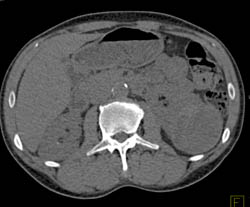

Renal Infarction